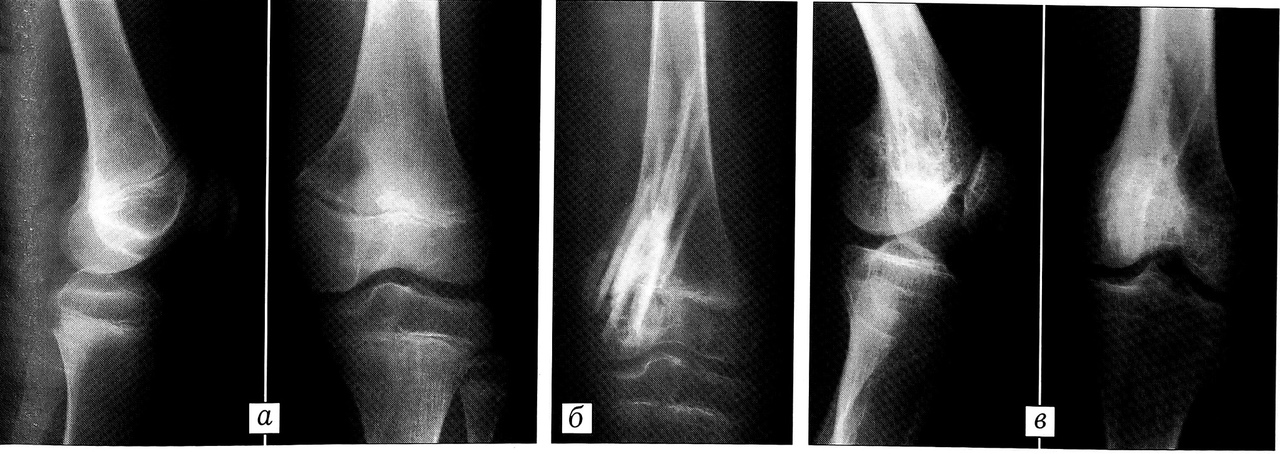

При «типичной» форме хондробластомы рентгенологическая картина характеризуется наличием эксцентрически расположенного остеолитического очага деструкции диаметром от 1,5 до 5 см, округлой или овальной формы, с четким контуром. От смежных отделов кости очаг отграничен полоской склероза. В половине наблюдений отмечались характерные крапчатые включения. В ряде случаев включения имели вид хлопьев ваты. Эксцентрическое расположение очага деструкции и рост опухоли приводили к истончению и «вздутию» коркового слоя. Разрушение коркового слоя с образованием экстраоссального компонента опухоли выявлено у 8 больных. Нередко определялись частично слившиеся периостальные наслоения, располагавшиеся на некотором удалении от очага, в метадиафизарном отделе (табл. 4, рис. 2).

Рис. 2. Больной X. 16 лет. Хондробластома проксимального метаэпифиза левой большеберцовой кости. Рентгенограммы в прямой и боковой проекции: разрушение ростковой пластинки; округлый очаг деструкции с крапчатыми включениями известковой плотности; частично слившиеся периостальные наслоения в отдалении от очага.

Рис. 8. Больной Т. 9 лет. Хондробластома дистального метаэпифиза левой бедренной кости. a — рентгенограммы до операции; б — непосредственно после операции (околосуставная резекция дистального метаэпифиза левой бедренной кости, пластика дефекта кортикальными аллотрансплантатами); в — рентгенограммы через 4 года после операции: рецидива нет, груботрабекулярная перестройка кости в зоне операции, закрытие зоны роста по внутренней поверхности, варусная деформация конечности на уровне левого коленного сустава.

У 8 пациентов вследствие разрушения части зоны роста опухолью и самим хирургическим вмешательством с возрастом развились укорочение и деформация конечностей (рис. 8), которые были устранены дополнительным хирургическим пособием.